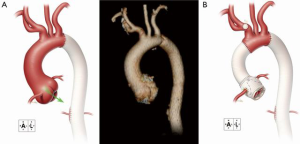

A 28-year-old man with suspected MFS was admitted to his local hospital for assessment after experiencing abdominal pain and heart palpitations. Although the patient had previously experienced a detached left retina and a pulmonary embolism, he had not undergone prior aortic or cardiac evaluation or repair. An echocardiogram revealed mild aortic valve regurgitation with aortic root dilatation and suggested a bicuspid aortic valve. A computed tomography scan confirmed a dilated aortic root (4.6 cm) and ascending aorta (5.0 cm), as well as enlargement of the proximal portion of the aortic arch (3.3 cm) (Figure 3A). The patient was referred to our center for further assessment. Aortic root and hemiarch replacement were indicated; because of the patient’s age and preference, a valve-sparing approach to ARR was desired, if feasible.

The patient’s chest was opened by using a standard median sternotomy. After a partial occluding clamp was placed on the innominate artery, an 8-mm graft was anastomosed to the artery for inflow during cardiopulmonary bypass. The ascending aorta was cross-clamped proximal to the innominate artery. Antegrade and retrograde cardioplegia were provided intermittently. After the aneurysm was opened, the aortic valve leaflets were examined. Large fenestrations were seen on all 3 leaflets, and there was fusion of the right and noncoronary leaflets (Figure 3B). The aortic valve was resected after determining it was unsuitable for valve-sparing ARR. The coronary arteries were mobilized on buttons of tissue. Starting with the three commissures, 2-0 braided polyester mattress sutures with felt pledgets were placed in the native annulus to anchor the composite valve graft (i.e., to perform a modified Bentall procedure). Additional annular mattress sutures with pledgets were then placed between the sutures at the commissures for a total of 15 sutures. The annulus was then sized to select an appropriate replacement valve. Once the patient was cooled to 24 °C and hypothermic circulatory arrest was initiated, the innominate artery was constricted with a Rumel tourniquet, and the pump flow was turned down to 1.5 L/min. The aortic clamp was removed, and a balloon perfusion catheter was placed into the left common carotid artery to provide bilateral antegrade cerebral perfusion. The lesser curvature of the transverse aortic arch was resected, and a rifampin-soaked, 24-mm tube graft was anastomosed end-to-end by using a running 4-0 polypropylene suture in a beveled hemiarch fashion. This anastomosis was then reinforced with 4-0 polypropylene mattress sutures with felt pledgets to ensure hemostasis. The innominate artery tourniquet was released, the balloon perfusion catheter was removed from the left common carotid artery, and flows were increased to a normal level as the graft was flushed of air and then clamped.

A “lifesaver” of autogenous pericardium was created and placed around the origin of the left coronary artery, which was then reattached with a running 6-0 polypropylene suture. The composite valve graft was trimmed just distal to the neo-sinus portion, and the two grafts were anastomosed end-to-end by using a running 3-0 polypropylene suture. Using a running 6-0 polypropylene suture, we reattached the right coronary artery reinforced with autogenous pericardium. The completed repair is shown in Figure 3C.